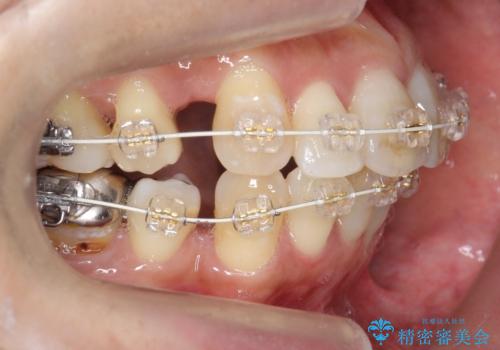

- 審美装置

- 3年4ヶ月

- 10-30回

歯の移動量が大きく、また、少し歯も動きにくかったため矯正治療に時間はかかりましたがしっかり並べて前突感も大きく改善しました。